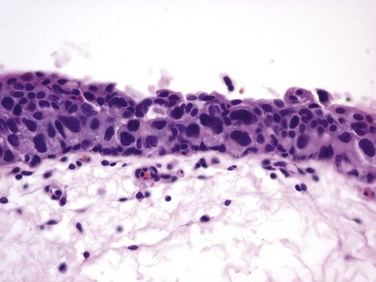

CIS is occasionally mischaracterized as “premalignant” (Sylvester et al, 2005), but it is actually a flat, noninvasive UC that is high grade by definition. Although confined to the urothelium in the same manner as stage Ta, CIS is regarded as a precursor for the development of invasive high-grade cancer.

CIS lesions are composed of severely dysplastic urothelium. Microscopically, the slide will demonstrate disorderly histology with nuclear atypia characteristic of high-grade malignancy; denudement of some or all of the mucosa due to loss of cellular cohesion sometimes complicates interpretation. A pathology report read as dysplasia or atypia can create confusion. Most pathologists consider mild examples of these entities to be benign. However, lesions interpreted as severe dysplasia or severe atypia are regarded as being the same entity as CIS (Epstein et al, 1998). Again, unambiguous communication between pathologist and urologist can minimize the risk for misinterpretation.